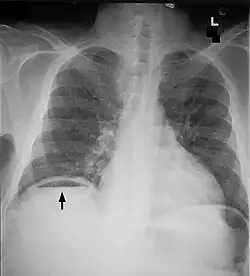

Bowel obstruction

Bowel obstructions are commonly secondary to adhesions, hernias, or cancer. Bowel obstruction can be an emergency requiring immediate surgery. Original testing and imaging include blood tests for electrolyte levels, and abdominal X-rays or CT scans. Treatment often begins with IV fluids to correct electrolyte imbalances. Obstructions may be complicated by ischemia or perforation of the bowel. These cases are surgical emergencies and often require bowel resection to remove the cause of obstruction.[13] Adhesions are a common causes of obstruction, and frequently resolve without surgery.[14]

Perforation

Bowel perforation presents with abdominal pain, free air in the abdomen on standing X-ray, and sepsis.[15][16][17] Depending on the cause and size, perforations may be medically or surgically managed. Some common causes of perforation are cancer, diverticulitis, and peptic ulcer disease.